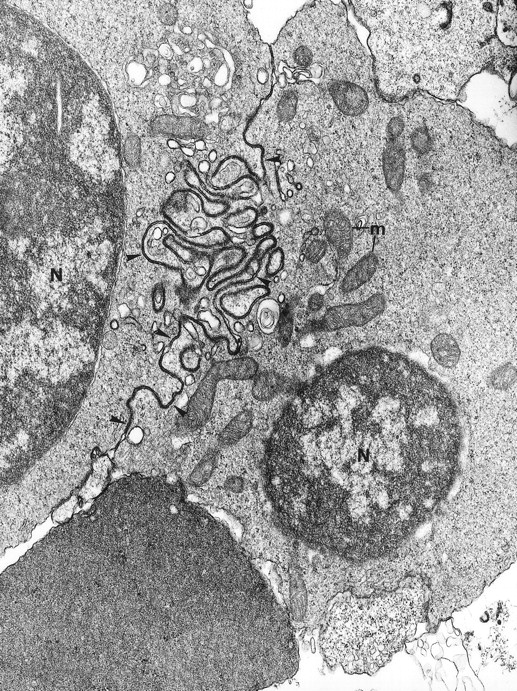

Electron microscopy confirmed the diagnosis of erythroblastic synartesis in the 3 patients. Plasma membranes of adjacent erythroblasts were joined by closely interdigitating processes (Fig2). Cytochemical demonstration of the peroxidatic activity of hemoglobin (not shown) allowed identification of maturation stages of the erythroblasts, because its level of intensity relates to the hemoglobin content of each cell. This technique showed that erythroblasts of the same maturation stage, as well as those of different maturation stages, were linked. Ribosomes were absent at sites of linkage via interdigitating process, corresponding with the nonbasophilic areas observed by light microscopy (Fig3a). At the junction sites, coated pits and rhopheocytosis vesicles were absent, probably because a macrophage expansion would find it impossible to penetrate this zone of tightly linked plasma membrane. Ferritin granules were never observed within these junctions. Junctions between erythroblasts had a characteristic morphology: resembling gap junctions, they were formed by 2 closely placed membranes joined by periodical structures every 150 Å, giving rise to a zipper-like appearance (Fig 3b). Isolated normoblasts often displayed picnotic nuclei and/or binuclearity. The 2 external leaflets of the plasma membrane of adjacent erythroblasts were separated by a constant space of 145 Å in patient 1, and 180 Å in patients 2 and 3.

Fig. 2.

The electron microscopic aspect of the bone marrow erythroblasts from patient 1: Cells are joined by interdigitating processes of the plasma membrane (arrowheads). They delineate areas of cytoplasm which are deprived of ribosomes (N, nucleus; m, mitochondria). Original magnification: ×21,000.